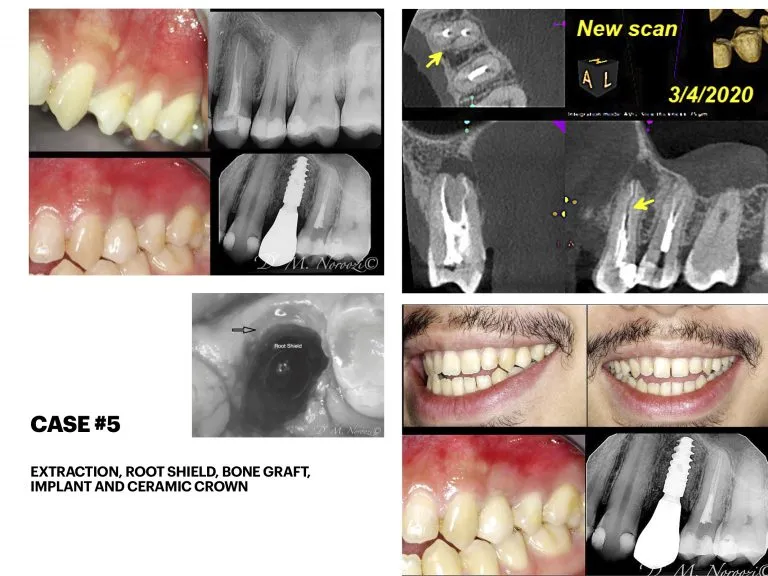

Before & Afters of Dental Implant Patients

Complete Dental Implant Cases Gallery

Surgical advances with SAME-DAY IMPLANTS in Vancouver BC

Using the most recent advances in dental implant technology, Dr. Noroozi is able to place single stage implants. These implants do not require a second procedure to uncover them but may require a minimum of six weeks of healing time before artificial teeth are placed. There are even situations where the implant can be placed at the same time as the tooth extraction and the artificial tooth can be inserted immediately following the implant placement – further minimizing your number of surgical procedures.

General Disclaimer: The results in the photographs are examples only and do not imply any certainty of the result of a procedure, and all outcomes are subject to the circumstances of the individual patient.